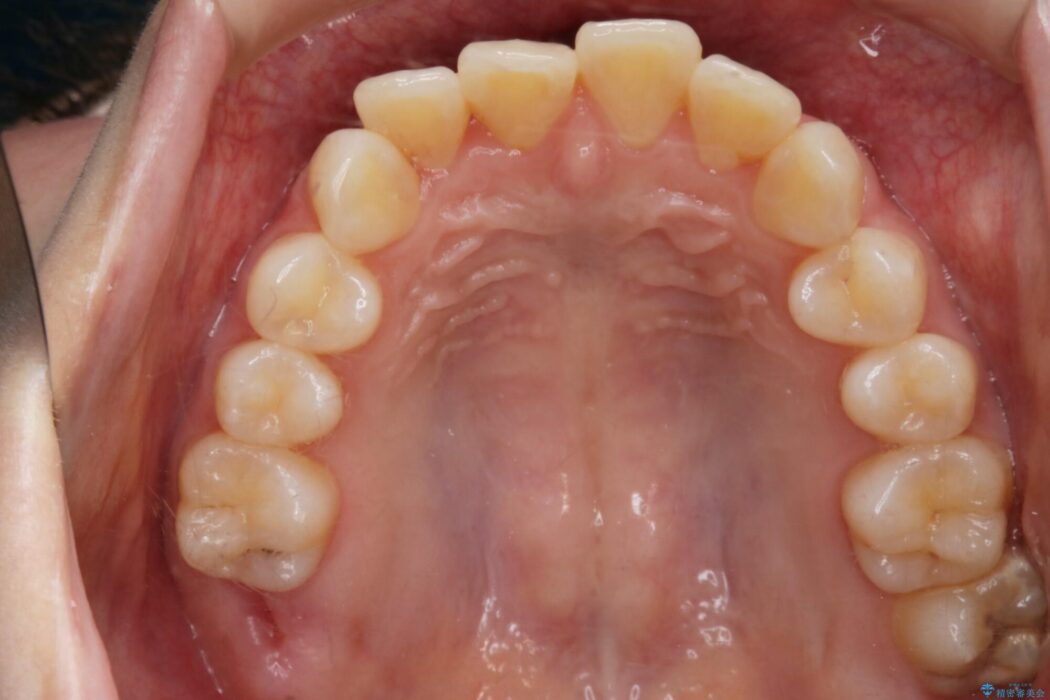

【20代女性】ブライダルに向けた矯正できれいなスマイルラインへ

- 患者様:20代女性

- 治療期間:1年10ヶ月

- 矯正装置:インビザライン コンプリヘンシブパッケージ

笑った時に見える歯並びをきれいにしたいとの主訴で来院されました。

ガタつきの度合いから抜歯は不要と判断しましたので、マイクロインプラントを用いて歯全体を遠心移動させていくことでねじれや噛み合わせのズレを改善していく計画を立てました。